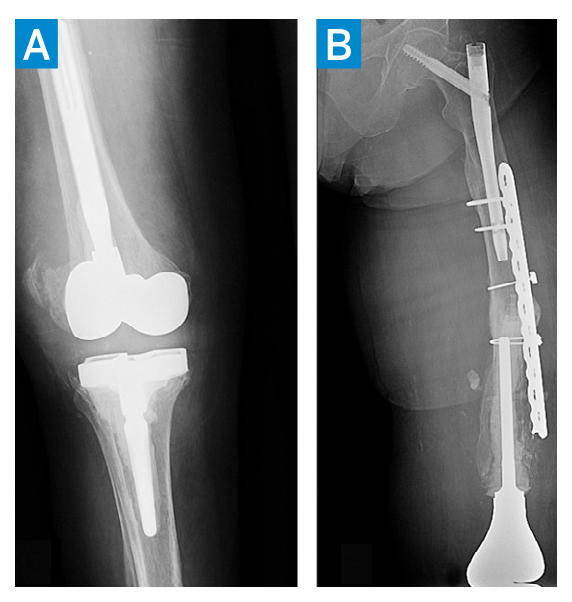

Several months later, the patient represented with bilateral knee pain (she had had a right knee replacement 10 years prior). Subsequent aspirations of both knees revealed PJI due to S. aureus despite suppressive antibiotics. The patient underwent a right knee both-component removal with insertion of an articulating antibiotic spacer (Figure 2A), followed a week later by both-component revision and partial resection of the remaining lateral femoral plate (Figure 2B). She responded well, completing IV antibiotics and being placed again on suppressive oral antibiotics.

Figure 2: AP views of the right knee following component removal and insertion of an articulating antibiotic spacer (A) and left knee component revision and partial resection of femoral plate (B).